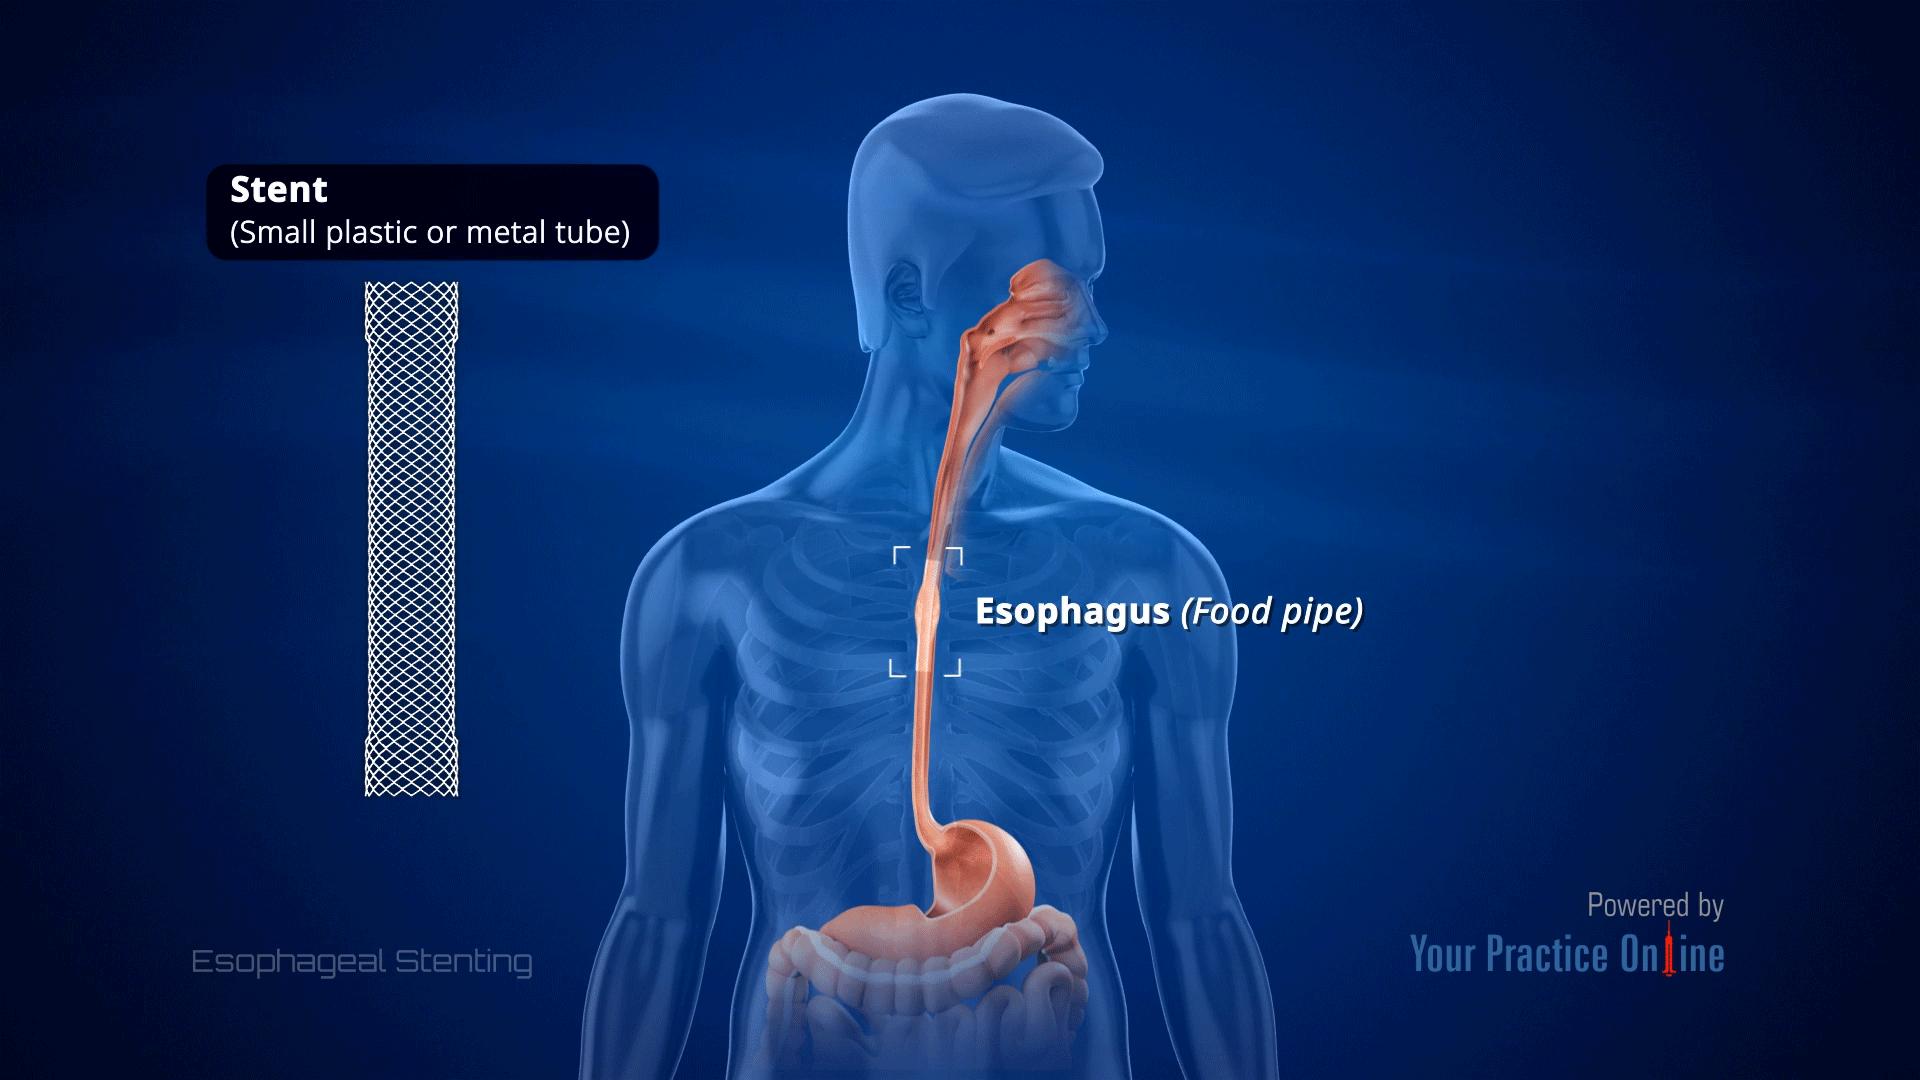

Esophageal Stenting Video Medical Video Library

Esophageal Stenting Video Medical Video Library